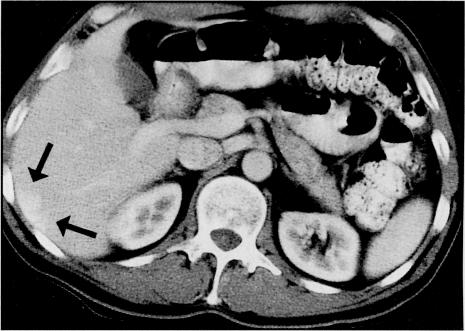

A 56-year-old man presented with intermittent rectal bleeding of six months' duration. Colonoscopy revealed three left colon polyps, one of which harbored adenocarcinoma. Endoscopic mucosal resection (band-assisted colonoscopic polypectomy) was successful. Endoscopic ultrasonography did not demonstrate any local or regional spread; however, abdominal computed tomography (CT) scan raised suspicion of an isolated metastasis to the liver. The patient's mother had recently died from metastatic colorectal cancer. When presented with the options of no surgery, postendoscopic mucosal resection, and CT-directed needle biopsy of the suspected isolated metastasis to the liver versus segmental resection of the flat adenoma site and wedge resection of the liver lesion for the maximum chance of a surgical cure, the patient opted for the surgical approach. Histopathology revealed no evidence of malignancy in the rectosigmoid colon, pericolonic lymph, or liver specimen. Awareness of increased risk of early cancer in flat adenomas with central depression is important because prompt recognition can lead to curative therapy.

一名56岁男性出现持续6个月的间歇性直肠出血。结肠镜检查发现左半结肠有3个息肉,其中1个含有腺癌。内镜黏膜切除术(带辅助结肠镜息肉切除术)成功。内镜超声检查未显示任何局部或区域扩散;然而,腹部计算机断层扫描(CT)扫描怀疑有孤立性肝转移。患者的母亲最近死于转移性结直肠癌。在面临不手术、内镜黏膜切除术后、对疑似孤立性肝转移进行CT引导下针吸活检,以及对扁平腺瘤部位进行节段性切除和对肝脏病变进行楔形切除以获得手术治愈最大机会的选择时,患者选择了手术方法。组织病理学显示,直肠乙状结肠、结肠周围淋巴结或肝脏标本中均无恶性肿瘤证据。认识到中央凹陷型扁平腺瘤早期癌变风险增加很重要,因为及时识别可导致治愈性治疗。